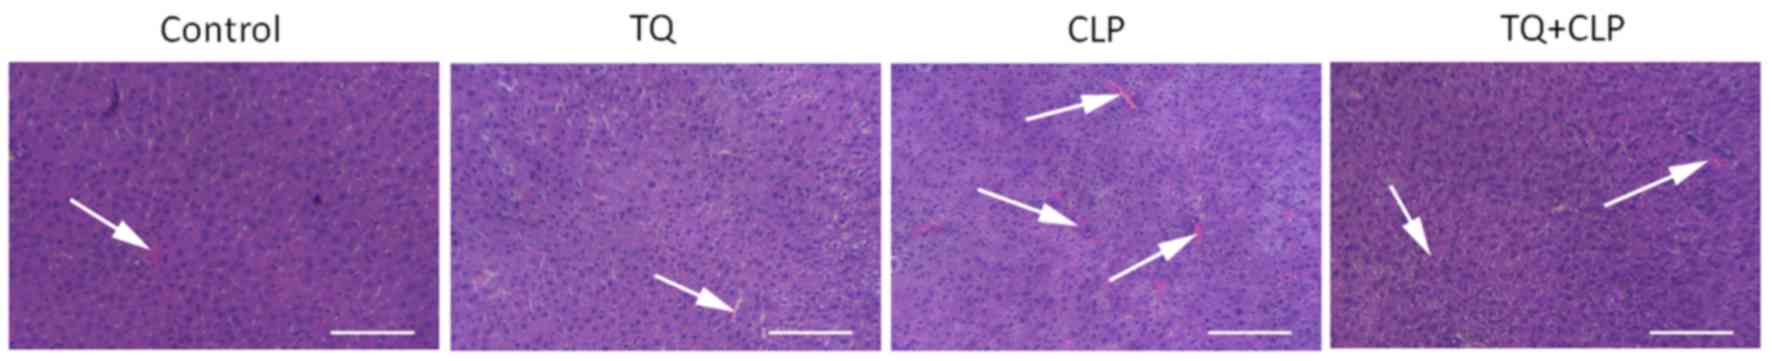

H&E staining was performed to evaluate the histopathological damage in LT (Fig. 2) and the results for the control and TQ groups revealed that hepatocytes were in regular shape and contained a large spheroidal nucleus. Contrastingly, the CLP group exhibited a marked liver injury demonstrated by hepatic strand disorganization, zonal necrosis, mononuclear cell infiltrations, centrilobular swelling, and sinusoidal and centrilobular congestions compared with the other groups. However, the administration of TQ to mice prevented the degenerative alterations in the hepatic structure induced by CLP.

Figure 2.

Histopathological damage in the liver tissue in the four groups of BALB/c mice subjected to various treatments. Arrows exhibited hepatic strand disorganization, zonal necrosis, centrilobular swelling, and sinusoidal and centrilobular congestions. Scale bar, 100 µm. CLP, cecal ligation and puncture; TQ, thymoquinone.